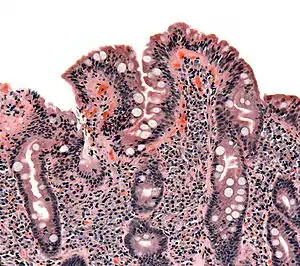

| The ileocecal valve prevents reflux of bacteria from the colon into the small bowel. Resection of the valve can lead to bacterial overgrowth. | |